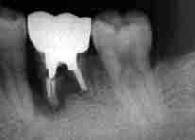

初診時 パノラマ |23部Dental写真

主訴は|2の脱離

|2脱離管を挿入して撮影

初診時口腔内およびX線所見:

若干の歯牙喪失と大量の補綴物が装着されてはいるが、清掃状態は比較的良好で、年齢の 割に歯槽骨の破壊は軽度。 脱離歯のポスト部分からは出血があり、歯根部の穿孔が疑われた。また、隣接する|3の 動揺は著明で歯根の破折が疑われた。

脱離したクラウンを挿入して、Dental写真を撮ってみると予想通りの結果であった。

根尖病巣と穿孔、それに歯根破折。まさに三重苦、しかも治療後1年間痛みと動揺に 悩み続けたという本人の訴えがヒシヒシと伝わってくる症例です。 元々は|23の連結冠だったそうで、予定通り治療が終了していればこのような 結果にならずにすんだものと思われます。

事の発端は、|2の根管治療不備による根尖病巣のようです。連結冠装着後、 同部の痛みが発症したために連結部を切断して金属ポストの除去。ココで第二の失敗→ 穿孔させてしまったようです。その結果、根管治療を断念してとりあえず体裁を整えるために 新たなポストコアーを作成して前装冠を装着。その際、|2の将来性を案じて |3との連結を行わず、また咬合圧を回避するために下顎との接触を極力避ける 補綴物を作成したようです。その結果|3に過剰な咬合圧がかかりついに|3 歯根破折を招いたようです。

最初の原因である|2の根管治療が最悪な状態でないだけに同情のすべき症例 であると伴に、多くの教訓を与えてくれた症例です。